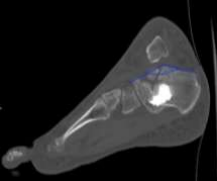

A computed tomography (CT) scan was performed to delineate the precise fracture anatomy, classify the fracture pattern according to the Sanders system, and inform treatment strategy.

The CT images revealed a Sanders type IV fracture, characterized by three fracture lines and four main posterior facet fragments (Figures 3 and 4). This complex fracture pattern demonstrates disruption of both the intra-articular and extra-articular components of the calcaneus. Furthermore, the crucial angle of Gissane measured approximately 165 degrees (Figure 5). This value significantly exceeds the normal range of 115-145 degrees, indicating significant posterior facet height loss and a potential for compromised joint congruity and long-term functional outcomes.